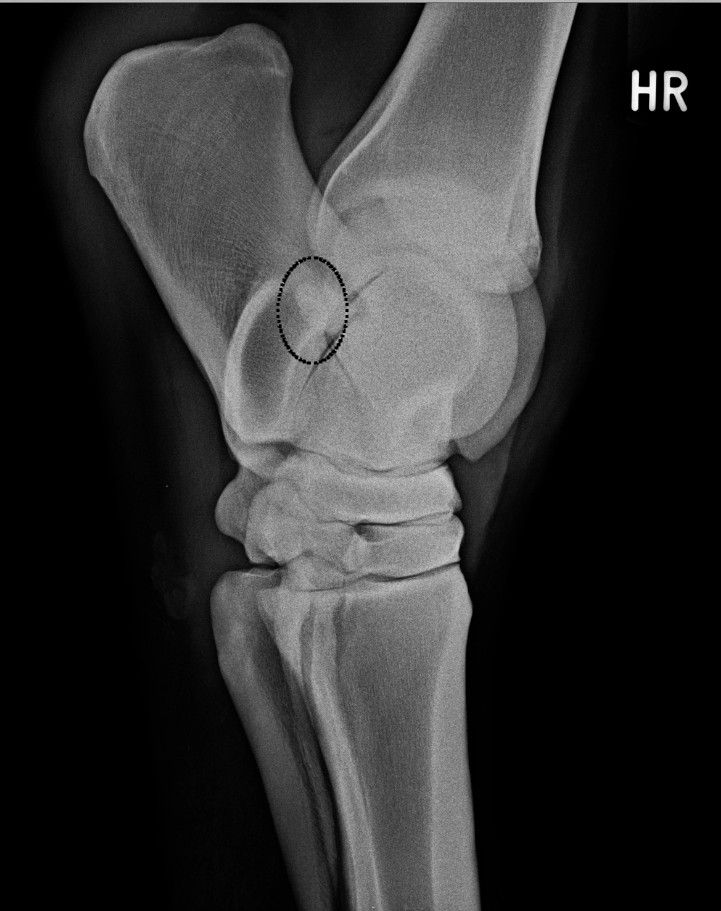

| Dire merci | Ben oui mais à priori la fracture est là depuis un moment .... donc bon ... étrange ... la "photo" de la fracture ![]() |

| Dire merci | oui elle m'avait montré un truc mais je voyais rien moi déjà devant son doigt ...je vois uniquement sur cette coupe, car c'est net. Le reste, on ne le voit pas sous tous les angles, d'où l'éventualité effectivement que ça ai pu passer à la trappe une précédente fois (genre l'an dernier) |

| Dire merci | oui c'est l'angle entre le 4 et le 2 qui est tout zarbi ça devrait être tout net comme ça (bon faut inverser hein ) : |

| Dire merci | oui ben je me demande si ce n'est pas la compression CD et le fait de ne pas avoir de logiciel pour ... parce qu'à la clinique c'étiat bien plus net ! autre vue oblique "en dessous" ![]() |